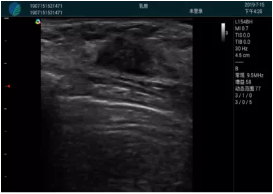

頸動脈血流充盈飽滿,無外溢

肝內(nèi)血管顯示清晰,血流敏感無外溢